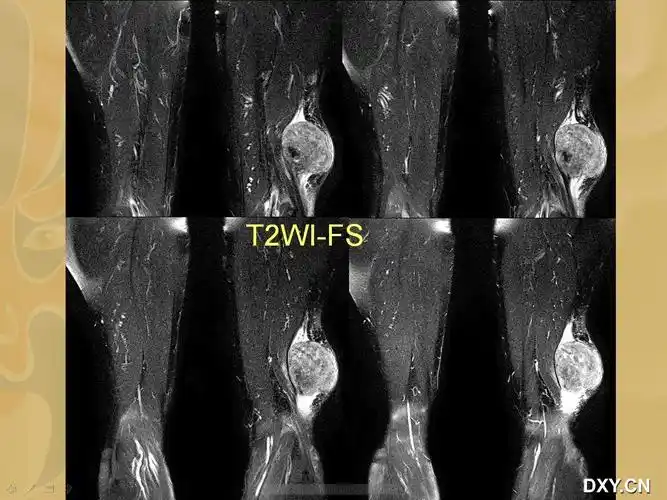

右大腿包块

随访 讨论腺泡状软组织肉瘤好发于青春期女性,多位于四肢深部肌肉或